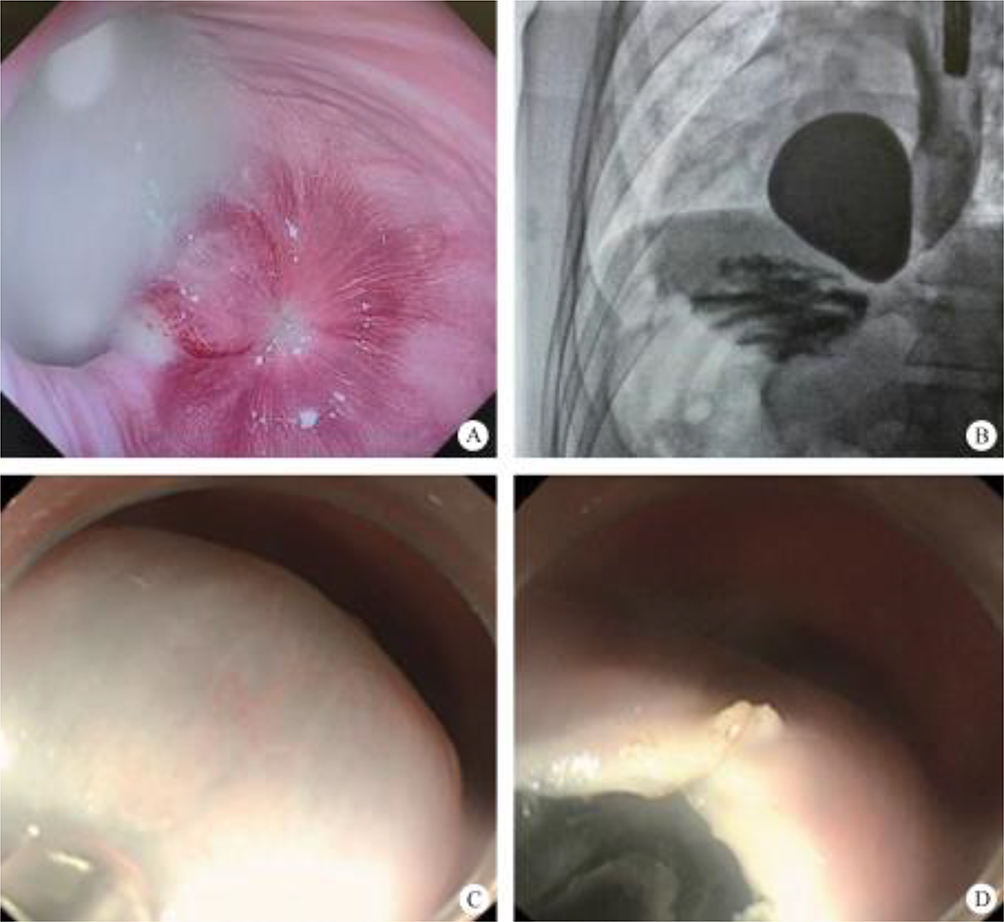

After endoscopic resection of circumferential esophageal lesions, almost 100% of patients experienced symptoms like esophageal stenosis and an inability to eat. Our team is the first in the world to carry out endoscopic autologous skin flap transplantation to prevent stenosis after endoscopic resection of esophageal circumferential lesions (figure 2.1), and 19 cases of autologous transplantation of skin flaps and simple placement of an esophageal stent for the prevention of esophageal stenosis were compared. The results showed that rate of stent removal for the group who had received an autologous skin flap transplantation was significantly reduced compared to the group with a simple esophageal stent (36.8%–78.9%). Currently, this research is also aimed at optimizing surgical and transplant methods, so as to improve the survival rate of skin flaps and to reduce the rate of occurrence of esophageal stenosis.

1. Peroral endoscopic myotomy (POEM). POEM has been widely used in the clinical treatment of achalasia; recently, applications in other parts of the human body have also been gradually emerging. In 2020, a study was conducted on a group of eight patients esophageal diverticulum and esophageal diverticulum treated by using POEM, also known as peroral diverticulum myotomy (D-POEM). D-POEM establishes a tunnel under the esophageal mucosa and incises the ridge between the diverticulum in the tunnel to make the diverticulum disappear. Postoperative follow-up of all patients, their preoperative symptoms were improved, and no adverse events were reported. Studies have shown that D-POEM has a certain effect on esophageal diverticulum, and that it is not affected by the position of the diverticulum and the length of the ridge between them, making it a safe and effective operation.